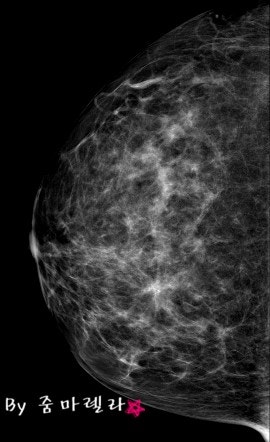

송탄의 유방암 검진은 일반적으로 유방조영술로 시행하는데, 유방조영술은 유방압박 후 유방의 상하, 유방의 내부와 외부를 엑스레이로 검사하는 것입니다. 암 여부를 구분할 수 있다고 합니다. 맘모톰 촬영 후 검사 결과지를 받아보실 수 있습니다. 병원에 가서 검사를 받는 것이 가장 좋습니다. 일반적인 치밀유방의 경우 유방조영술을 통해 얻을 수 있는 정보가 제한적이기 때문에 이 경우에도 유방초음파검사를 통해 유방초음파에 이상이 있는지 등을 추가로 시행하는 것이 좋습니다. 낭종. 혹의 모양과 카테터의 변화를 자세히 관찰할 수 있고 인체에 무해하며 젊은 환자와 임산부가 언제든지 확인할 수 있다는 장점이 있다. 초음파를 단독으로 사용하는 것이 대체 불가능한지 물으셨습니다. 고위험군이거나 40세 이상의 여성이라면 미세석회화, 종양, 구조적 뒤틀림을 찾기 위해 두 가지 검사를 동시에 받는 것이 최선이라고 해석합니다. 송탄유방암검진을 통해 조직검사가 필요한 경우 조직이 악성인지를 판단하는 것이 매우 중요하기 때문에 빠르고 안전한 유방암 검진을 위해 전체생검과 맘모톰을 이용합니다. 병변의 삽입과 제거는 국소마취 하에 이루어지기 때문에 통증에 대한 부담이 적고 흉터가 거의 남지 않아 환자가 크게 걱정하지 않고 검사를 받을 수 있다. 유방질환 치료에 적합하도록 종양을 제거할 수 있으나 맘모톰 수술 전에 정확한 검사가 이루어져야 합니다. 유방조영술 또는 유방조영술은 악성일 수 있거나 크기와 수가 증가한 종양을 확인하는 데 사용할 수 있습니다. 통증이 있거나 겉으로 보이는 종양이 있는지 주의 깊게 검사한 후 맘모톰 수술을 시행합니다. 국가건강검진을 시행하는 병원이 조직검사와 같은 정밀검사를 할 수 없는 곳이라면 검사결과와 발급된 유방조영상 데이터를 가지고 유방전문센터로 가기가 번거로울 것이다. 원스톱으로 진행되는 MRI 검사도 가능하며, 환자가 이미 검사 데이터를 가지고 있다면 정확한 진단에 도움이 되며, 같은 검사를 반복할 필요가 없으므로 휴대하는 것이 좋습니다. , 유방암은 다른 암과 달리 다양한 치료를 통해 잠재력이 크며 생존율이 높지만 앞으로 암의 수가 증가할 것으로 예상되므로 유방암은 고위험군과 같은 관리 가능한 질병으로 전환될 것으로 예상됩니다. 혈압, 당뇨병 등 앞으로 가장 중요한 것은 조기에 진단하고 치료를 시작하는 것입니다. 유방암을 예방하는 가장 효과적인 방법은 정기적인 유방암 검진이라고 할 수 있습니다 지속적인 치료가 필요한 병원을 선택하더라도 신중한 분들에게 건강한 유방수술은 너무 오래 기다릴 필요 없이 바로 확인할 수 있습니다 . 조직검사가 필요한 경우 당일 검사가 가능하도록 대학병원급 의료장비로 유방암 진단 시 정확한 검사를 시행할 수 있도록 최선을 다하겠습니다. 최근에는 환자의 연령이 점점 젊어지고 재발률도 높기 때문에 정기적인 검사만이 최선의 방법입니다. 오랜 진료 경력의 민러지 원장님께서 직접 검진부터 치료까지 1:1 맞춤 진료를 진행하고 있으니 송탄 유방암 검진 외에도 갑상선 검진도 진행해보시길 바랍니다! 광고 후에 계속하십시오. 다음 주제저작자 취소 건강한 유수술 재생 0 좋아요 0 좋아요 공유 0:00:00 재생 음소거 00:00 00:00 라이브 전체 화면 해상도 설정 currentTrack 자막 비활성화 재생 속도 NaNx 해상도 자막 설정 비활성화 옵션 글꼴 크기 배경색 재생 속도 0.5 x 1.0x(기본값) 1.5x 2.0x 알 수 없는 오류가 발생했습니다. 도움말 보기 음소거되었습니다. HD로 재생하려면 이 동영상에 라이선스를 부여하세요. 설정에서 해상도를 변경해 보세요. 더 알아보기 0:00:00 Collapse/ExpandHealthyBreastSurgery #HealthyBreastSurgery (이 게시물은 HealthyBreastSurgery에서 작성했습니다.)